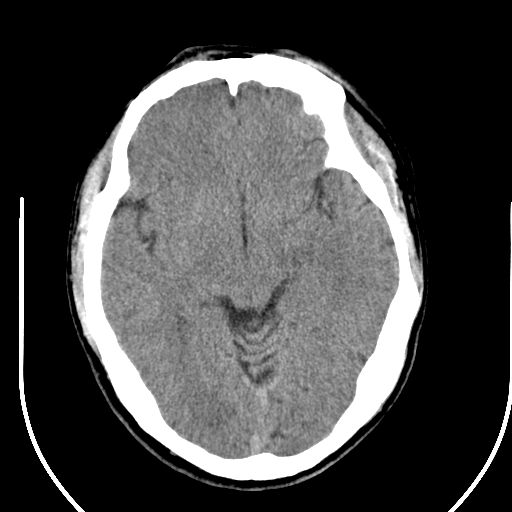

边缘清晰,没有占位效应,不像脑沟,结合ct值,软化灶可能吧

与脑沟没关系,小软化灶或陈旧性感染吧!

软化灶。